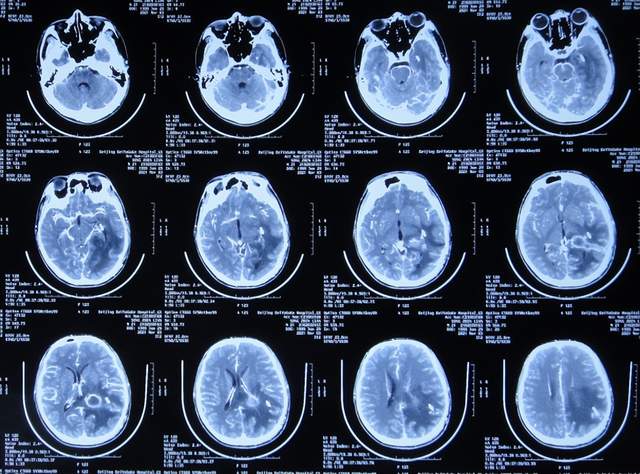

出院后5个月即2021年9月中旬,出现偶尔头痛的症状,因此于出院后7个月后即2021年11月10日,第2次来到李小勇脑脊液科;入院时:时有头痛(图-26),身体其他正常;查头颅CT示左侧颞角扩张(图-27)。

图-26:2021年11月10日入院时

图-27:入院时头颅CT

入院后2天即2021年11月12日,给予了颞角分流管调整术;术后第2天查头颅CT示颞角仍扩张(图-28)。

图-28:2021年11月14日头颅CT

入院治疗14天即2021年11月24日,查头颅CT示颞角缩小(图-29),患者头痛基本消失(图-30)。

图-29:2021年11月24日头颅CT

图-30:2021年11月24日

2022年1月4日(李小勇脑脊液科第2次治疗55天)出院。出院时:头痛已消失1月余(图-31),身体一切正常,查头颅CT示未见异常(图-32)。

图-31:2022年1月4日出院时

图-32:出院时头颅CT